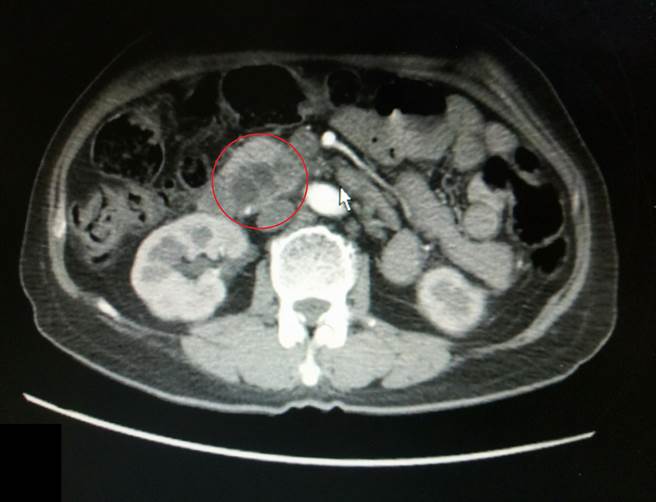

苗栗62歲劉姓婦人連續幾天發現上腹痛和小便呈現茶色的情況而就醫,經檢查發現她的黃疸和胰臟腫瘤指數偏高、膽管和胰管都阻塞,且胰臟頭有腫瘤,經切片檢查後確診為胰臟癌,並在大千綜合醫院積極治療中。院方提醒,胰臟癌初期症狀不明顯,常被誤認為是腸胃道不適而忽略,一旦確診大多為晚期,因此留意胰臟癌的三大典型症狀:黃疸、上腹痛、體重減輕,是非常重要的指標。

大千綜合醫院肝膽腸胃科主任洪吉來表示,胰臟癌常出現的症狀包含黃疸、上腹痛及體重減輕,且胰臟癌很容易轉移、擴散及侵犯重要血管,其中有85到95%的病人為胰腺癌,不但預後差,復發率也很高。目前最好的治療方法是手術,但因多數病人發現得晚,在臨床上只有15%的病人有機會接受手術治療,其餘多只能以化學及放射治療為主。因此,若能早期發現與治療,才是對抗胰臟癌的重要關鍵。

洪吉來建議,高風險族群一定要定期接受腹部超音波、電腦斷層等影像檢查,才能及早揪出胰臟癌。雖然胰臟癌是相當難纏的癌症,但高危險族群若能定期接受檢查,並留意胰臟癌的症狀,就能早期發現、早期治療,成功對抗胰臟癌的威脅。